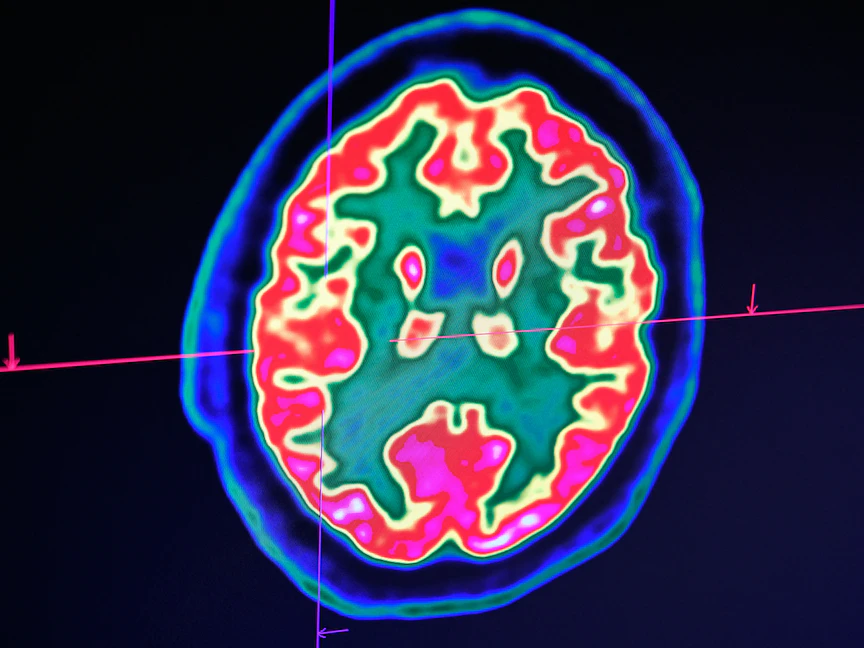

تحتفظ أدمغتنا بالعديد من الذكريات السعيدة والمؤلمة، لكن أين تحديداً يتم حفظ تلك الذكريات؟

وتوضح الدراسة أنَّ ذكريات الخوف عن بعد التي تشكلت في الماضي البعيد يتم تخزينها بشكل دائم في وصلات بين الخلايا العصبية الموجودة في قشرة الفص الجبهي.

وقشرة الفص الجبهي هي الجزء الأمامي من الدماغ ويعرف العلماء أن تلك المنطقة تُسهم في بعض الوظائف التنفيذية مثل اتخاذ القرارات والسلوك الاجتماعي، كما أنها مسؤولة أيضاً عن تعديل السلوك الاجتماعي وتنسيق الأفكار والأفعال وتُخزن فيها أيضاً الذكريات قصيرة المدى.

إلا أنَّ تلك الدراسة تُشير للمرة الأولى إلى أن دوائر ذاكرة الفص الجبهي يتم تنشيطها تدريجياً بعد الأحداث الصادمة، ويلعب هذا التنشيط دوراً حاسماً في كيفية نضوج ذكريات الخوف إلى الأشكال المستقرة في القشرة الدماغية للتخزين الدائم.

ووجد الباحثون أن مجموعة صغيرة من الخلايا العصبية داخل قشرة الفص الجبهي تنشط أثناء الحدث الصادم الأولي ثم يتم إعادة تنشيطها أثناء استدعاء تلك الذكريات في المستقبل.